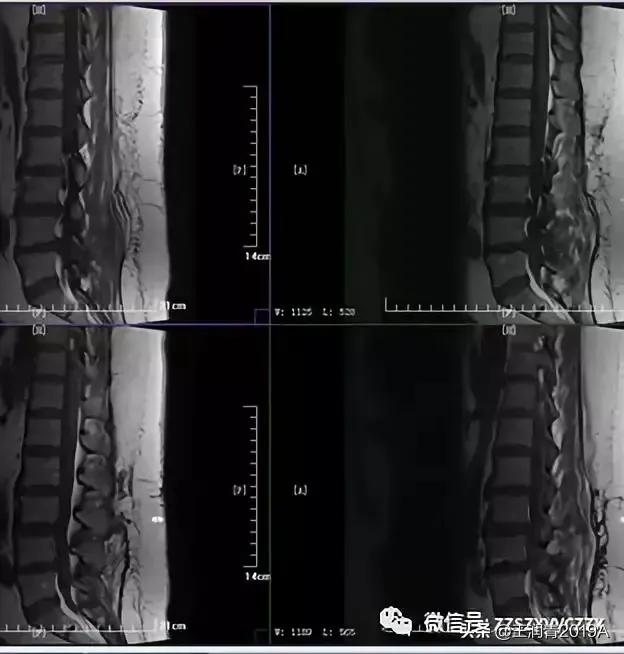

1、腰椎MR平扫检查(图2-3)

腰椎MRI:腰1-2、腰2-3、腰3-4、腰4-5及腰5-骶1椎间盘突出;平腰4椎体层面椎管内占位。

2、腰椎MR增强检查:平腰4椎体层面椎管内异常信号影,考虑腰椎间盘髓核脱出影(腰4-5)(图4-8)